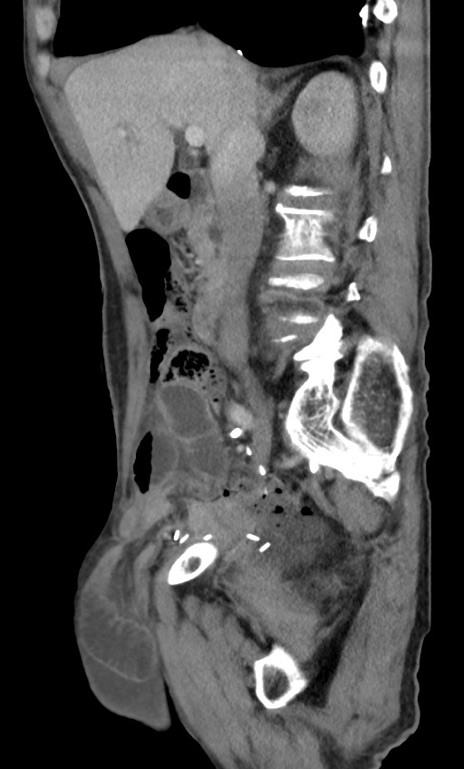

症例3(矢状断像)

症例

【症例】 70歳代男性

【主訴】右鼠径部腫瘤、疼痛

【現病歴】本日朝より上記主訴あり、受診。

【既往歴】膀胱癌にて膀胱全摘、両側尿管皮膚瘻

【データ】WBC 5600、CRP 0.56